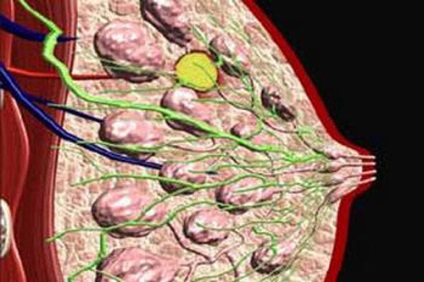

Fibroadenomatosis este un proces în care imaturi țesăturile formă de celule, localizate în glandele mamare, extinde - și raportul dintre țesutul conjunctiv și epitelial au schimbat foarte mult, iar fibrotic apar, chistice și alte modificări.

- fibroadenomatosis Difuz. În caz contrar, acesta poate fi numit distrasă. El a fost numit astfel pentru că buzunarele sunt distribuite în glandele - pot găsi o mare varietate de noduli, care arata ca compactare mici granular jart dureros atunci când este apăsat.

- Localizate san fibroadenomatosis. Chiar și numele este clar că, de exemplu, în contrast cu subtipurile anterioare ale bolii, este mai concentrată la nivel local. Când sondare a observat, de asemenea, durere. Nodulii au o margine clară, sub piele detectabilă rugozitatea non-uniform.

- Vatra. Acest subtip benigne a bolii este caracterizată prin faptul că țesutul glandular este treptat înlocuit fibros. Cea mai mare parte palpat sigiliu, dar acestea nu sunt întotdeauna dureroase, uneori, ele nu provoacă nici cea mai mică disconfort.

- Nodale. Pentru aceasta patologie se caracterizează prin nodal subtipul suprainfectia localizata a tesutului mamar cu senzații dureroase în zonele în care a avut loc expansiunea.

- Chistică. Cu varietate de boli apar multicompartimentală sigiliu de tip asemănător cu chisturi si avand contururi destul de buna.

- fibroadenomatosis fibrotice. În ciuda tautologia în titlu, acesta este, de asemenea, tipul de boală, care se caracterizează printr-o predominanță a creșterii țesutului fibros în timpul formării focilor în glandele.